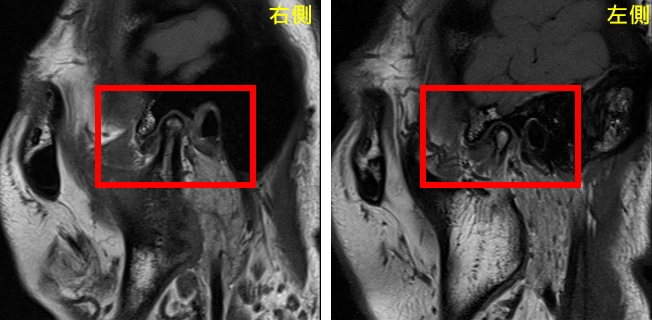

圖:治療前圖。曾小姐雙罹患側顳顎關節障礙症候群,出現肌筋膜疼痛症、關節盤不可復移位及骨關節炎。

經專業評估後,由口腔顎面外科呂明怡主治醫師施行關節腔玻尿酸注射,並由智慧賦能中心林志峰主任進行震波治療。透過跨專業協作,針對病因進行整體性處理,短短一個月內,曾小姐的顳顎關節疼痛、臉頰緊繃、喉嚨異物感及肩頸痠痛等症狀即大幅減輕。隨著持續治療,生活品質顯著提升,也逐漸找回自信與笑容。

圖:治療後圖。進行玻尿酸治療與震波治療三個月後,病友曾小姐狀況大幅改善。